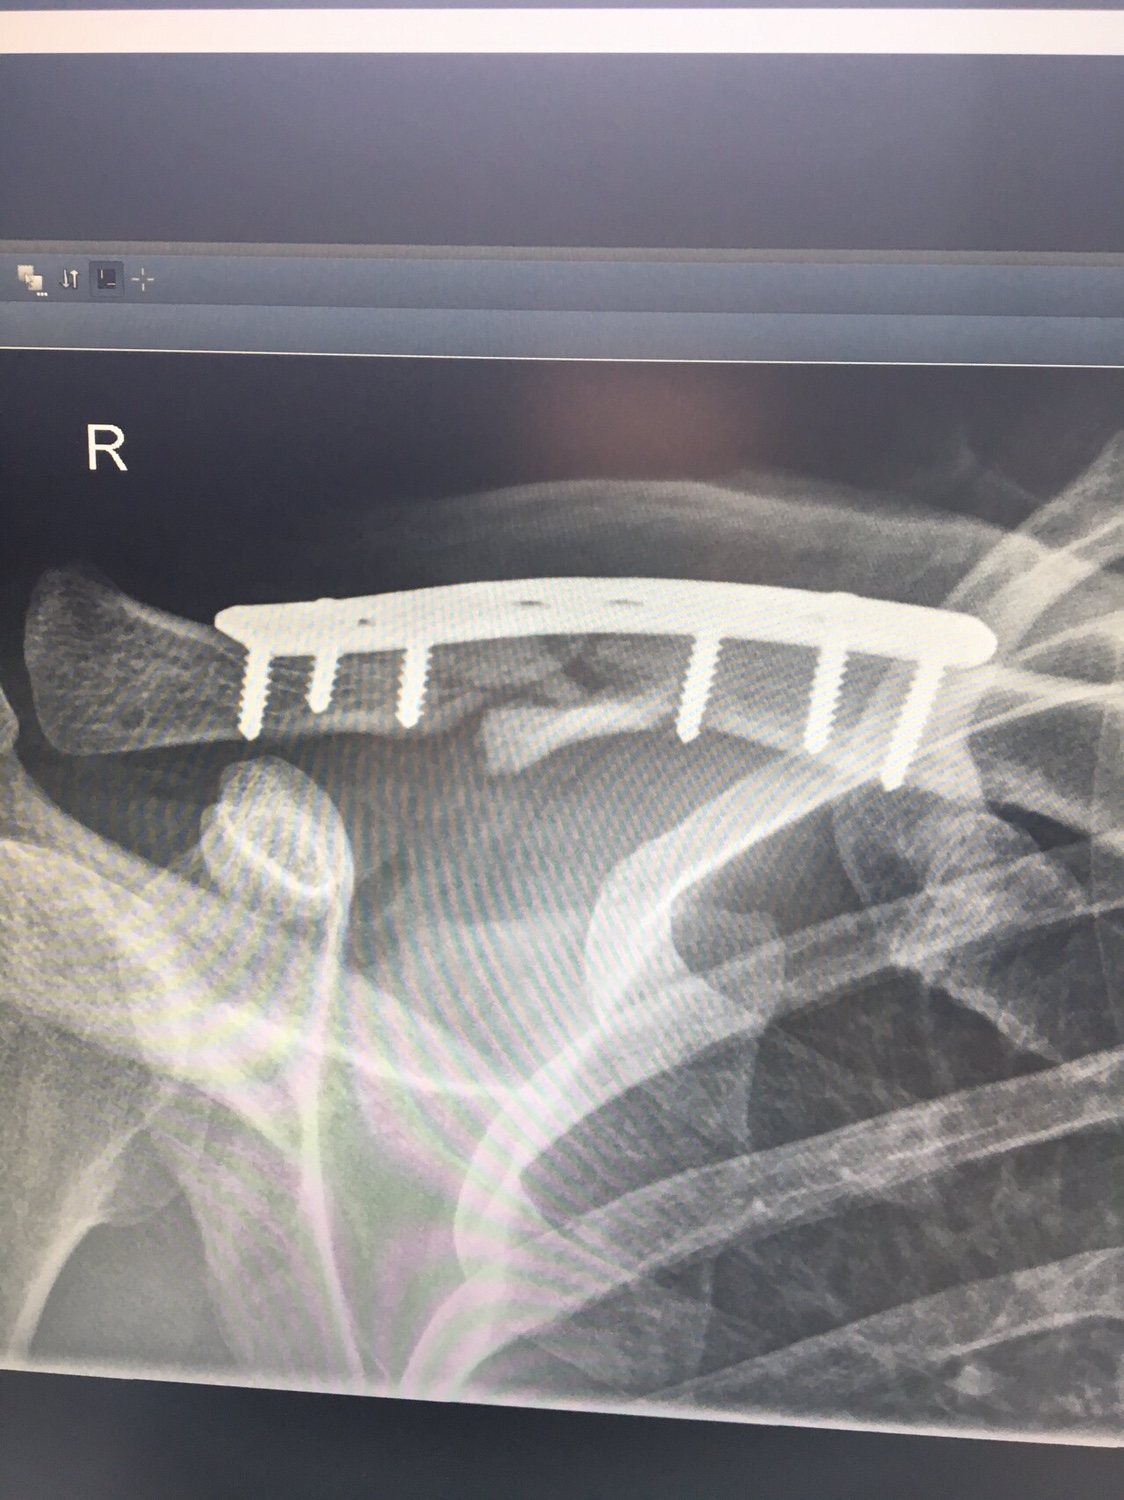

Udo-MH hat geschrieben:Also ich kann ja mal meine 2 cent beisteuern. Auch wenn es nicht das gleiche ist. Ich hatte einen Clavicula RE Trümmerbruch. Die Erste OP war gelaufen und mir wurde eine viel zu dünne Titanplatte eingeschraubt. Die Trümmer von der Assiärztin mit Nähfaden umwickelt. Wenn gewünscht hau ich auch Röntgenfotos rein, was aber für mich zweitrangig ist.

Ok. Erste Platte nach 3 Montaen und der Entfernung des Gilchristverbandes gebrochen. 2. OP. Dickere Platte und Knochenchips aus dem Beckenkamm zu einen Ei geformt um den Bruch. Weil der erste Versuch gescheitert war wurde "nachgefragt". Ich nehme alle 2-3 Tage Diclofenac wegen meines Bandscheibenvorfalls. Das hätte ich lt. Chefarzt NICHT nehmen dürfen. Es verhindert Callusbildung (Knochenverheilung). Dieser Heilprozess ist einer Entzündung gleichzusetzen. Da ich nun Entzündungshemmer nahm war das Ergebnis gleich null.

Die Platte ist nun schon seit ca. 2,5 Jahren drin und ich werde sie wohl auch nicht entfernen lassen. Da in 80% der OP´s das Schlüsselbein wieder bricht.